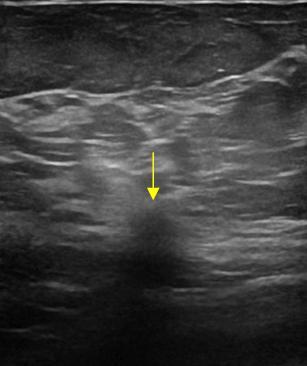

Ung thư vú

Ung thư vú - Ảnh 3

» Thông tin: Nữ giới – 62 tuổi.

» Lâm sàng: Kiểm tra sức khỏe.